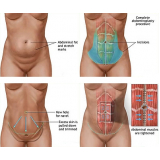

Abdominoplastia com Lipo

Há momentos em que é necessário ter por perto profissionais qualificados e dedicados à pronta recuperação do paciente. A FF Cirurgia Plástica oferece e coloca à sua disposição o que existe de mais atualizado em procedimento cirúrgico para abdominoplastia com lipo. Com o objetivo de levar qualidade à vida dos clientes, a instituição oferece infraestrutura adequada às necessidades de cada um: cuidado médico humanizado, realizado através de dedicação, profissionalismo e amor.

Você precisa de um consultório médico que realize abdominoplastia com lipo com segurança!